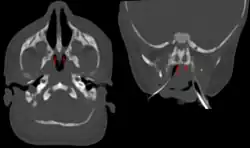

Bilateral membranous choanal atresia in CT scan | |

Choanal atresia is a congenital disorder where the back of the nasal passage (choana) is blocked, usually by abnormal bony or soft tissue (membranous) due to failed hole development of the nasal fossae during prenatal development. It causes persistent rhinorrhea, and with bilateral choanal atresia, an obstructed airway that can cause cyanosis and hypoxia.

Choanal atresia causes closure of the posterior choanae in the nasal cavity. Around 30% of these affect just the bone, while around 70% affect both bone and membranes. Bones affected can include the body of the sphenoid bone, the vomer, the medial pterygoid process of the sphenoid bone, and the horizontal plate of the palatine bone.[1]

Diagnosis is confirmed using CT scan.[1]This is also useful for differential diagnosis.[1]